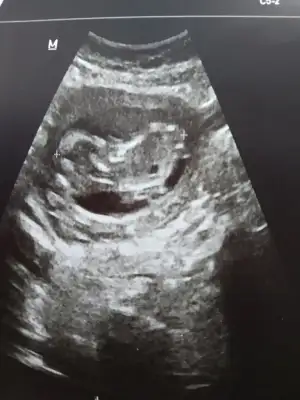

Canım bizede 12+5 de tahminde bulunurmusun karından usd dr bir tahminde bulundu ama net değil dedi🤗

• image.webp

image.webp

16 KB · Görüntüleme: 63